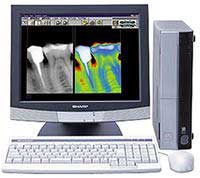

歯科検診では,多くの人を、照明も暗く、唾液で表面も光って見える状態でみていかなければなりませんのでこのような虫歯は見落とされてしまいます。当院はデジタルX線システムというレントゲンを導入し、このような見落としを極力防ぎ、患者様にモニター上で虫歯をご確認いただきます。

デジタルX線システムとは

従来のX線はフィルムに放射線を当てて像をやきつけていました。そのため、現像している間待たなければならず、また、現像ミスやフィルムの劣化のために再撮影しなければならないことがありました。デジタルX線システムはCCDセンサーに放射線を当ててコンピューター解析を行って画面上で確認するため、再撮影の可能性が非常に少なくなりました。しかも、現像の手間がないため,待ち時間がありません。

従来のX線はフィルムに放射線を当てて像をやきつけていました。そのため、現像している間待たなければならず、また、現像ミスやフィルムの劣化のために再撮影しなければならないことがありました。デジタルX線システムはCCDセンサーに放射線を当ててコンピューター解析を行って画面上で確認するため、再撮影の可能性が非常に少なくなりました。しかも、現像の手間がないため,待ち時間がありません。

そして、従来は判断のつきかねる大きさであった虫歯でも発見できるようになり、画像補正によって患者様にも虫歯の場所と大きさを説明することができるようになったのです。

そして、従来は判断のつきかねる大きさであった虫歯でも発見できるようになり、画像補正によって患者様にも虫歯の場所と大きさを説明することができるようになったのです。

さらに、従来のX線とくらべて被爆量が10分の1以下となりました。10枚撮影しても従来の1枚分より放射線量が少ないのです。お子様や妊婦さんには非常に有益なシステムと思われます。